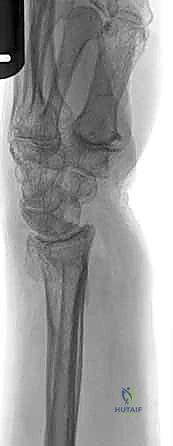

صورة طبية توضح كسر الناتئ الإبري

صورة لكسر في رأس الزند

توضيح لكسور الجزء الكردوسي الكردوسي

استخدام الأشعة السينية في التشخيص

1. الأشعة السينية (X-rays): بوضعيات متعددة (أمامية خلفية، وجانبية دقيقة). الوضعية الجانبية الحقيقية (True Lateral) حاسمة لاكتشاف أي خلع جزئي في المفصل (DRUJ).